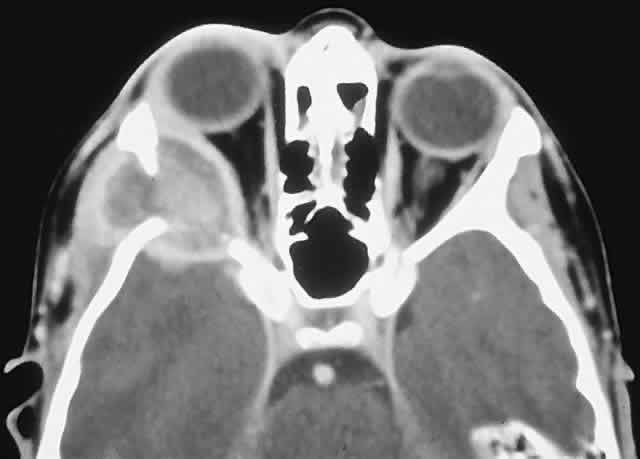

IMAGING. Chondrosarcomas appear as well-defined osteolytic lesions with stippled or mottled densities indicative of mineralization (Fig. 10). Higher-grade tumors tend to have irregular margins with nonuniform calcification in the form of amorphous cloudlike densities.125 The noncalcified regions show T1 signal intensities lower than or equal to gray matter on MRI. T2 signals are isointense to the cortex, and the masses usually display moderate enhancement.121,124,126,127

Fig. 10. This 46-year-old man with a history of midline chondrosarcoma resected 3 years previously presented with a right optic neuropathy. A. CT revealed recurrent tumor in the form of a heterogeneous mass involving both ethmoidal sinuses and orbit. Mottled areas of mineralization are apparent in the matrix of the lesion. B. The tumor was resected through an orbitocranial approach, and the histology revealed a grade 2 chondrosarcoma composed of hypercellular cartilage with lacunae containing binucleated chondrocytes (hematoxylin-eosin, × 50). He remains free of recurrence after 4 years.